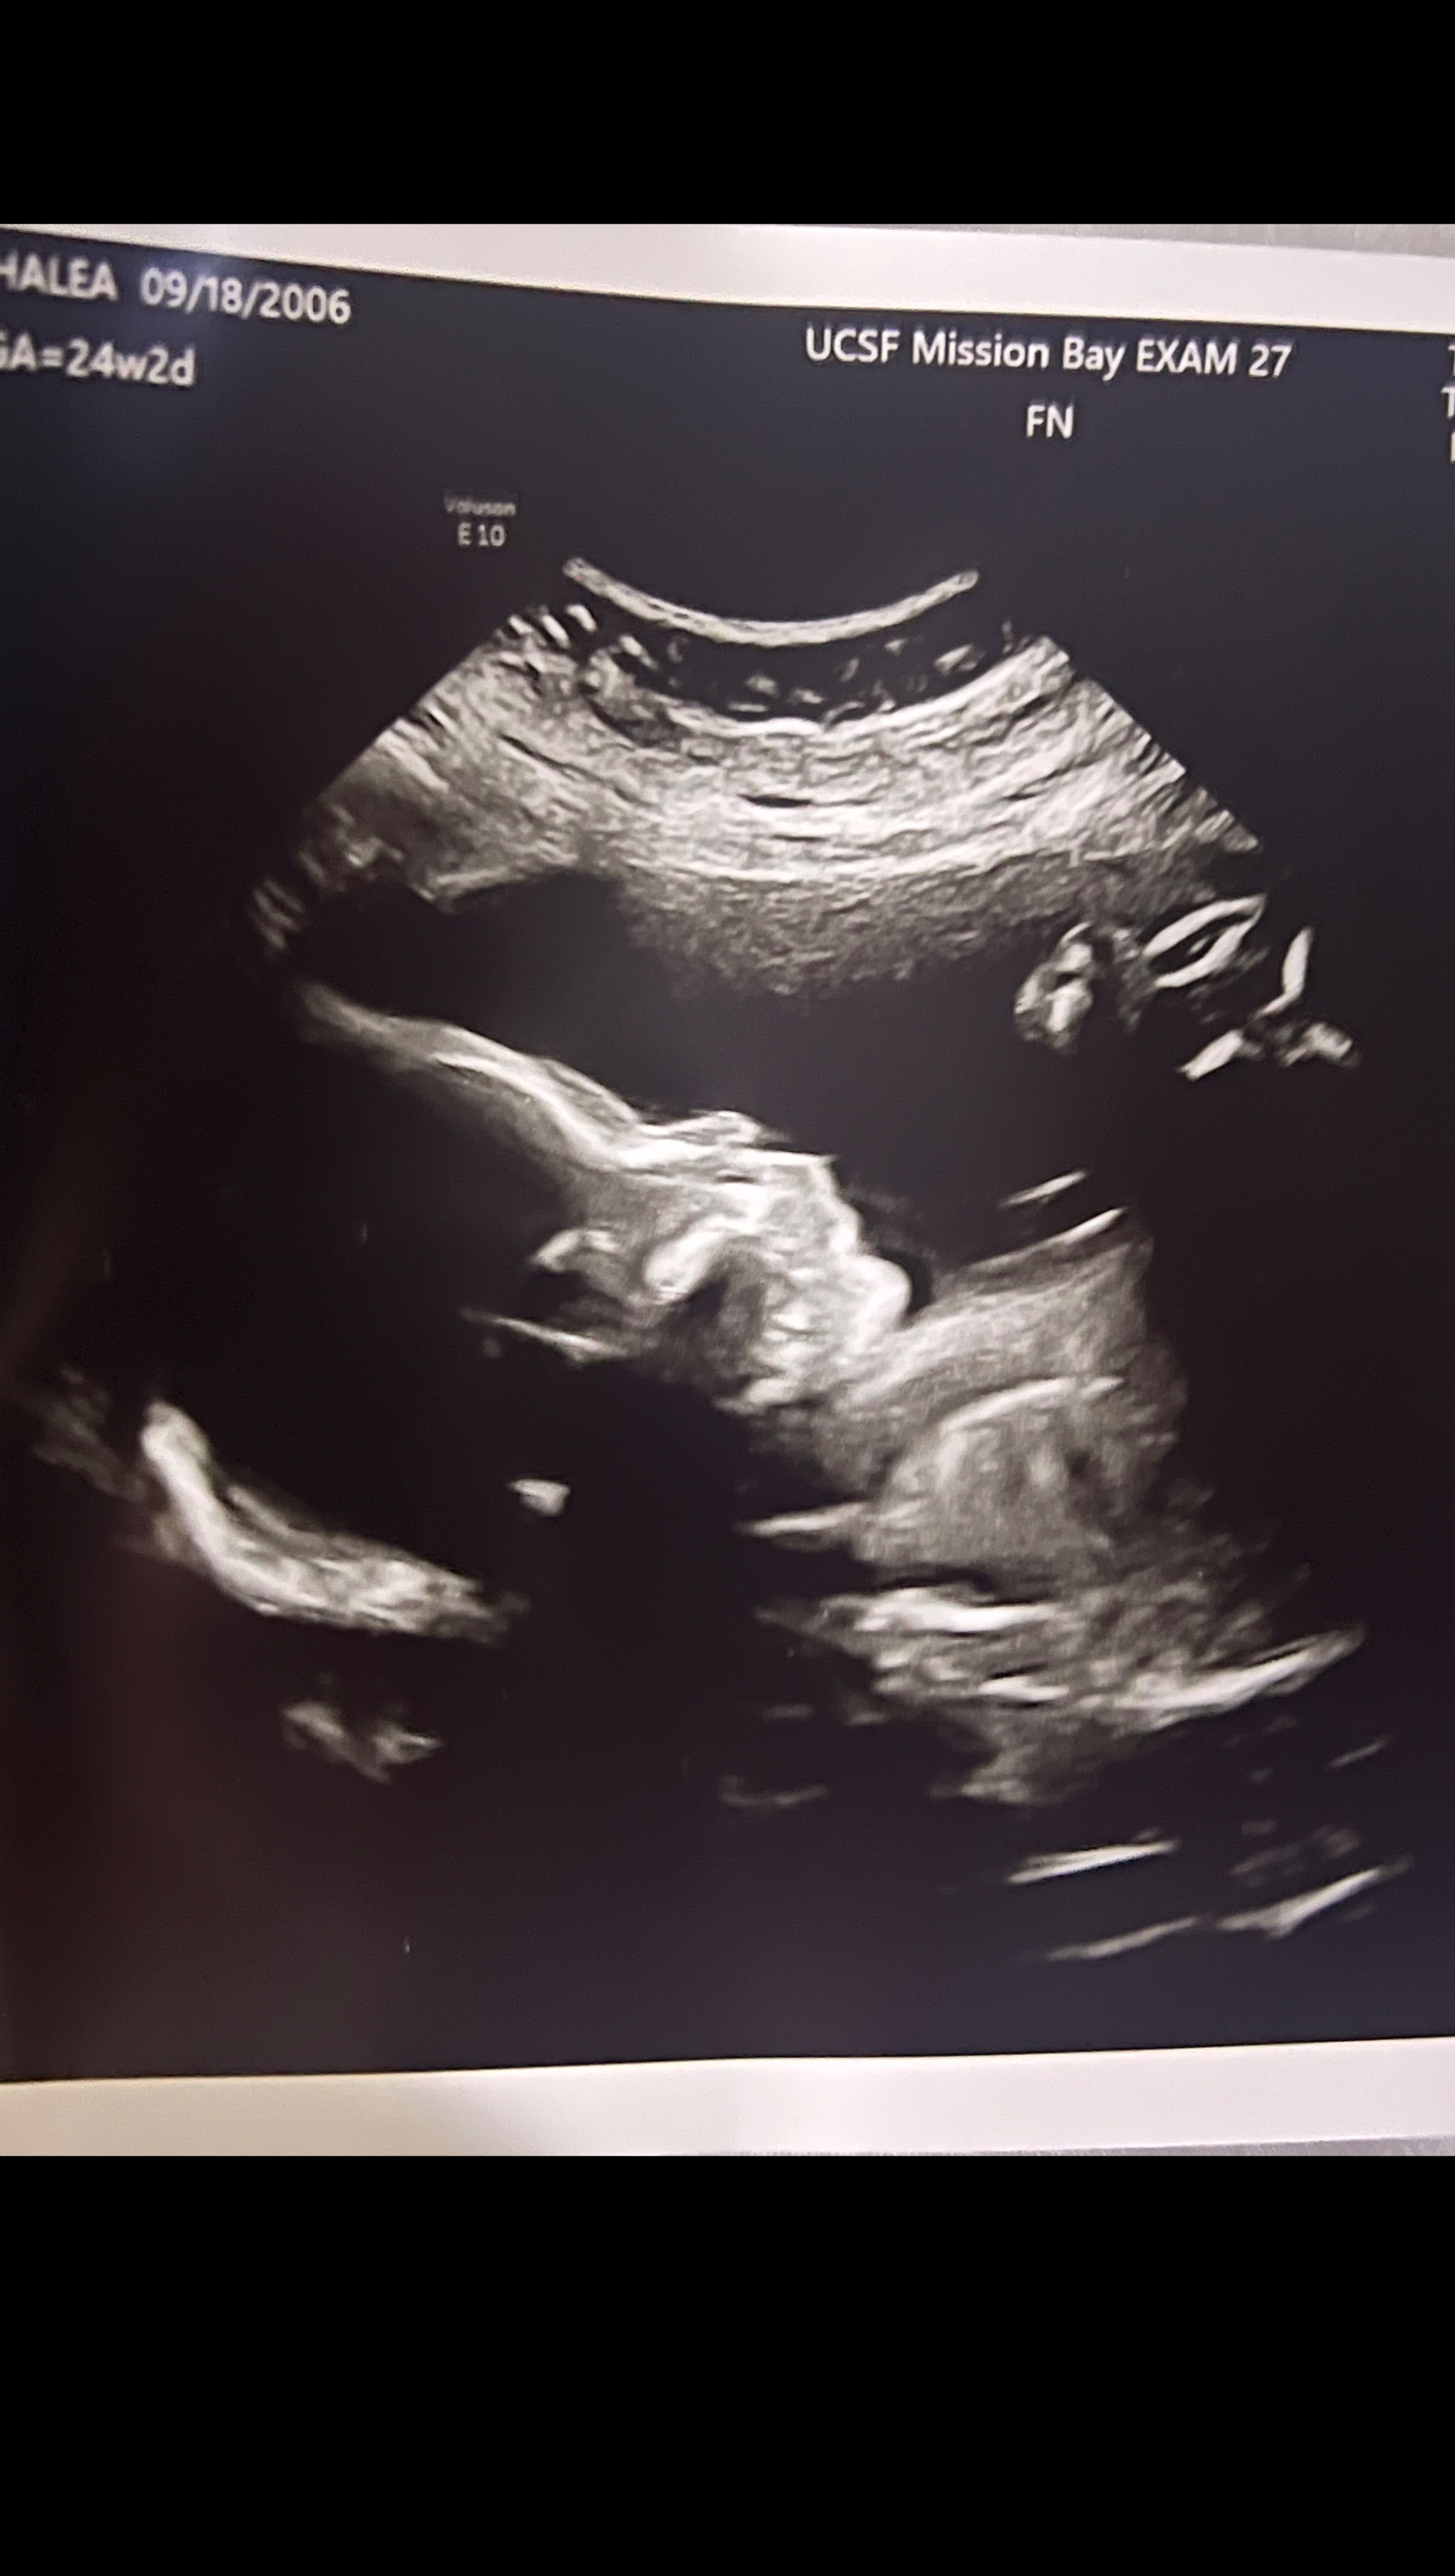

Hi, I'm setting up this account for Damien Gonzalez's unborn child. The sudden loss of a strong community youth leader has left a burden in our hearts and left the mother of his unborn child in need of support to be able to sustain the family they planned together. Damien was so excited to be a father, he was working with the community and was always a helping hand. The young warrior would talk about raising his child and how he would teach him sports and how he planned to put him to sleep every night. He was looking forward to the birth of his son to be the first to hold him skin to skin so he would build the strong bond with his junior. Damiens child was ripped away from the chance of meeting his father and in this we ask for your prayers and support to ease the pain in raising his child.

Being that the due date is so close mother has to focus on health while preparing to raise her child alone. Please support during these hard times economically we all know in San Francisco its hard being a single parent we weren't prepared for this.